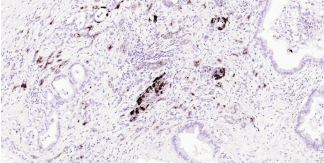

Immunohistochemical analysis of paraffin embedded human pancreas tissue slide using IHC0343H (Human Osteopontin Kit).

Immunohistochemical analysis of paraffin embedded human pancreatic cancer tissue slide using IHC0343H (Human Osteopontin Kit).